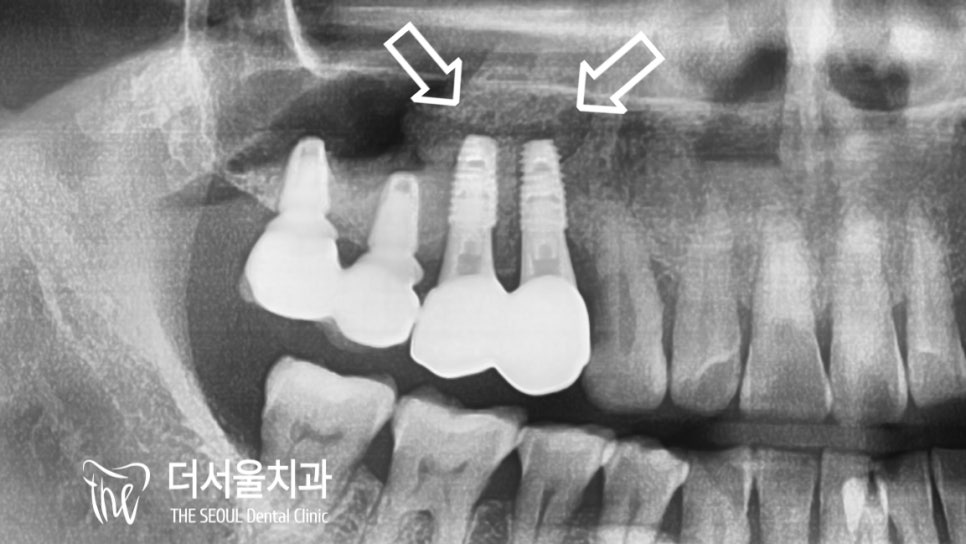

뿌리쪽을 들여다 봤을 때

어둡게 보여지는 ‘염증’ 들도 관찰되었죠.

뿌리 끝이 어두워져 있는 것이 확인되죠?

뼈와 막이 박리가 된 것을

확인을 한 뒤에 그 속으로

뼈 이식재를 이식해드린 뒤

픽스쳐 2개를 식립했습니다.

뼈 이식재는 혈액과 만나게 되면

골 융합 과정을 거치게 되며

엑스레이로 확인을 했을 때에

하얗게 보여집니다.